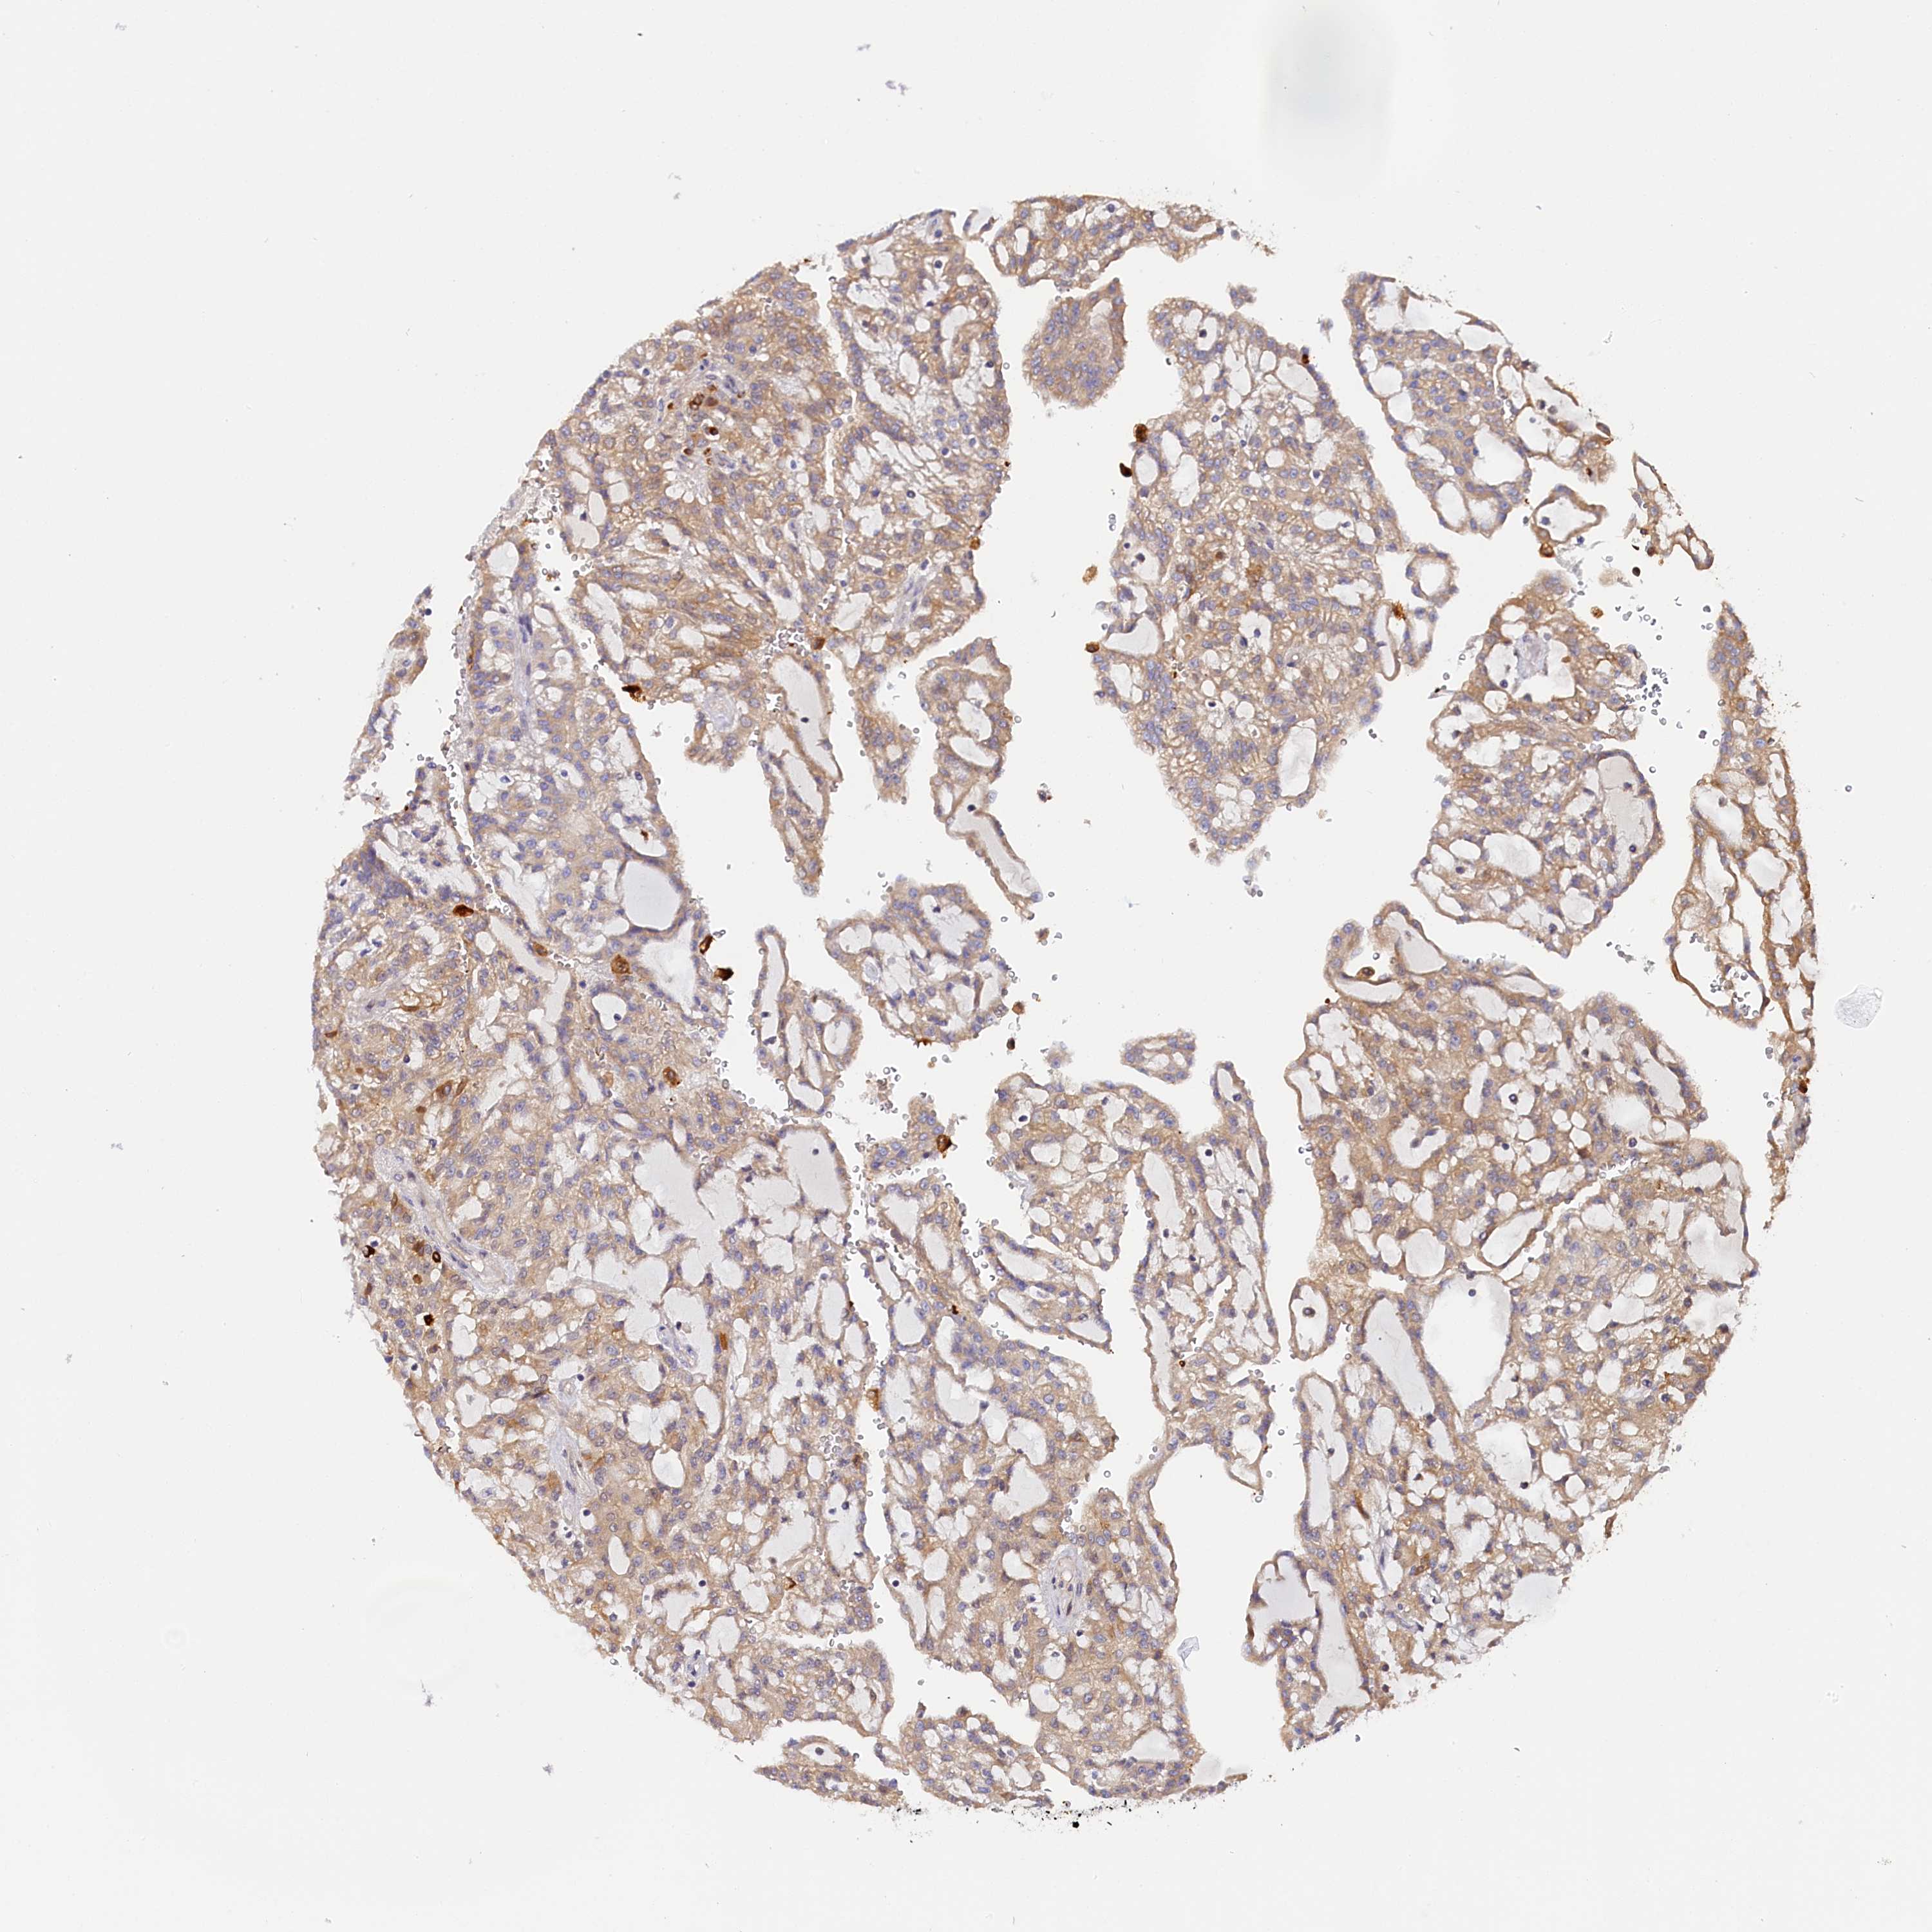

KIDNEY RENAL PAPILLARY CELL CARCINOMA (TCGA) - Interactive survival scatter ploti

The Survival Scatter plot shows the clinical status (i.e. dead or alive) for all individuals in the patient cohort, based on the same data that underlies the corresponding Kaplan-Meier plots. Patients that are alive at last time for follow-up are shown in blue and patients who have died during the study are shown in red.

The x-axis shows the expression levels (FPKM) of the investigated gene in the tumor tissue at the time of diagnosis. The y-axis shows the follow-up time after diagnosis (years). Both axes are complimented with kernel density curves demonstrating the data density over the axes. The top density plot shows the expression levels (FPKM) distribution among dead (red) and alive patients (blue). The right density plot shows the data density of the survived years of dead patients with high and low expression levels respectively, stratified using the cutoff indicated by the vertical dashed line through the Survival Scatter plot. This cutoff is automatically defined based on the FPKM cutoff that minimizes the p-score. The cutoff can be changed by dragging the vertical line or by entering a cutoff value in the square labeled "Current cut-off".

Under the Survival Scatter plot the p-score landscape (black curve; left axis) is shown together with dead median separation (red curve; right axis). Dead median separation is the difference in median mRNA expression between patients who have died with high and low expression, respectively. It is calculated as follows: median FPKM expression of dead patients with high expression - median FPKM expression of dead patients with low expression. This is intended to aid the user in visually exploring custom cutoffs and the associated p-scores and dead median separation.

Individual patient data is displayed and can be filtered by clicking on one or more of the category buttons on the top of the page. Categories describing expression level and patient information include: high, low, alive, dead, female, male and tumor stages. The scale of the x-axis can be toggled between linear and log-scale by clicking on the "x log" button. Mouse-over function shows TCGA ID, patient information and mRNA expression (FPKM) for each patient.

& Survival analysisi

Kaplan-Meier plots summarize results from analysis of correlation between mRNA expression level and patient survival. Patients were divided based on level of expression into one of the two groups "low" (under cut off) or "high" (over cut off). X-axis shows time for survival (years) and y-axis shows the probability of survival, where 1.0 corresponds to 100 percent.

KATNB1 is not prognostic in Kidney Renal Papillary Cell Carcinoma (TCGA)